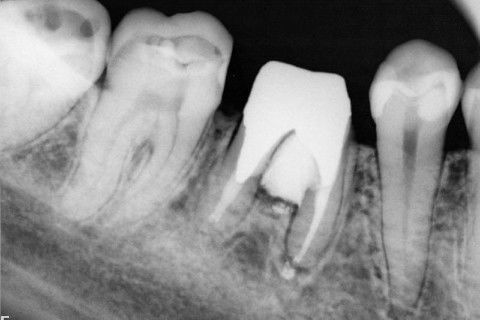

Retratamento de Canal, Tratamento de Perfuração, Restauração Provisória com Resina, Núcleo e Provisório.

RETRATAMENTO DE CANAL, TRATAMENTO DE PERFURAÇÃO, RESTAURAÇÃO PROVISÓRIA COM RESINA, NUCLEO E PROVISÓRIO.